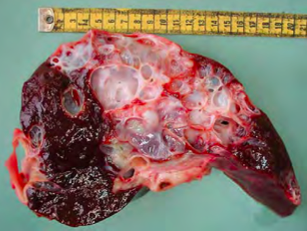

Massive hepatic necrosis

Involves entire lobule or contiguous lobules

Although this type of necrosis is commonly severe, the name massive indicates involvement of the whole lobule.

One of the most common causes of massive hepatic necrosis is the condition known as hepatosis dietetica of swine.

Hepatosis dietetica has been associated with generation of free radicals and deficiency of Vitamin E/Selenium.

MASSIVE HEPATIC NECROSIS IN HEPATOSIS DIETETICA OF SWINE. CUT SURFACE